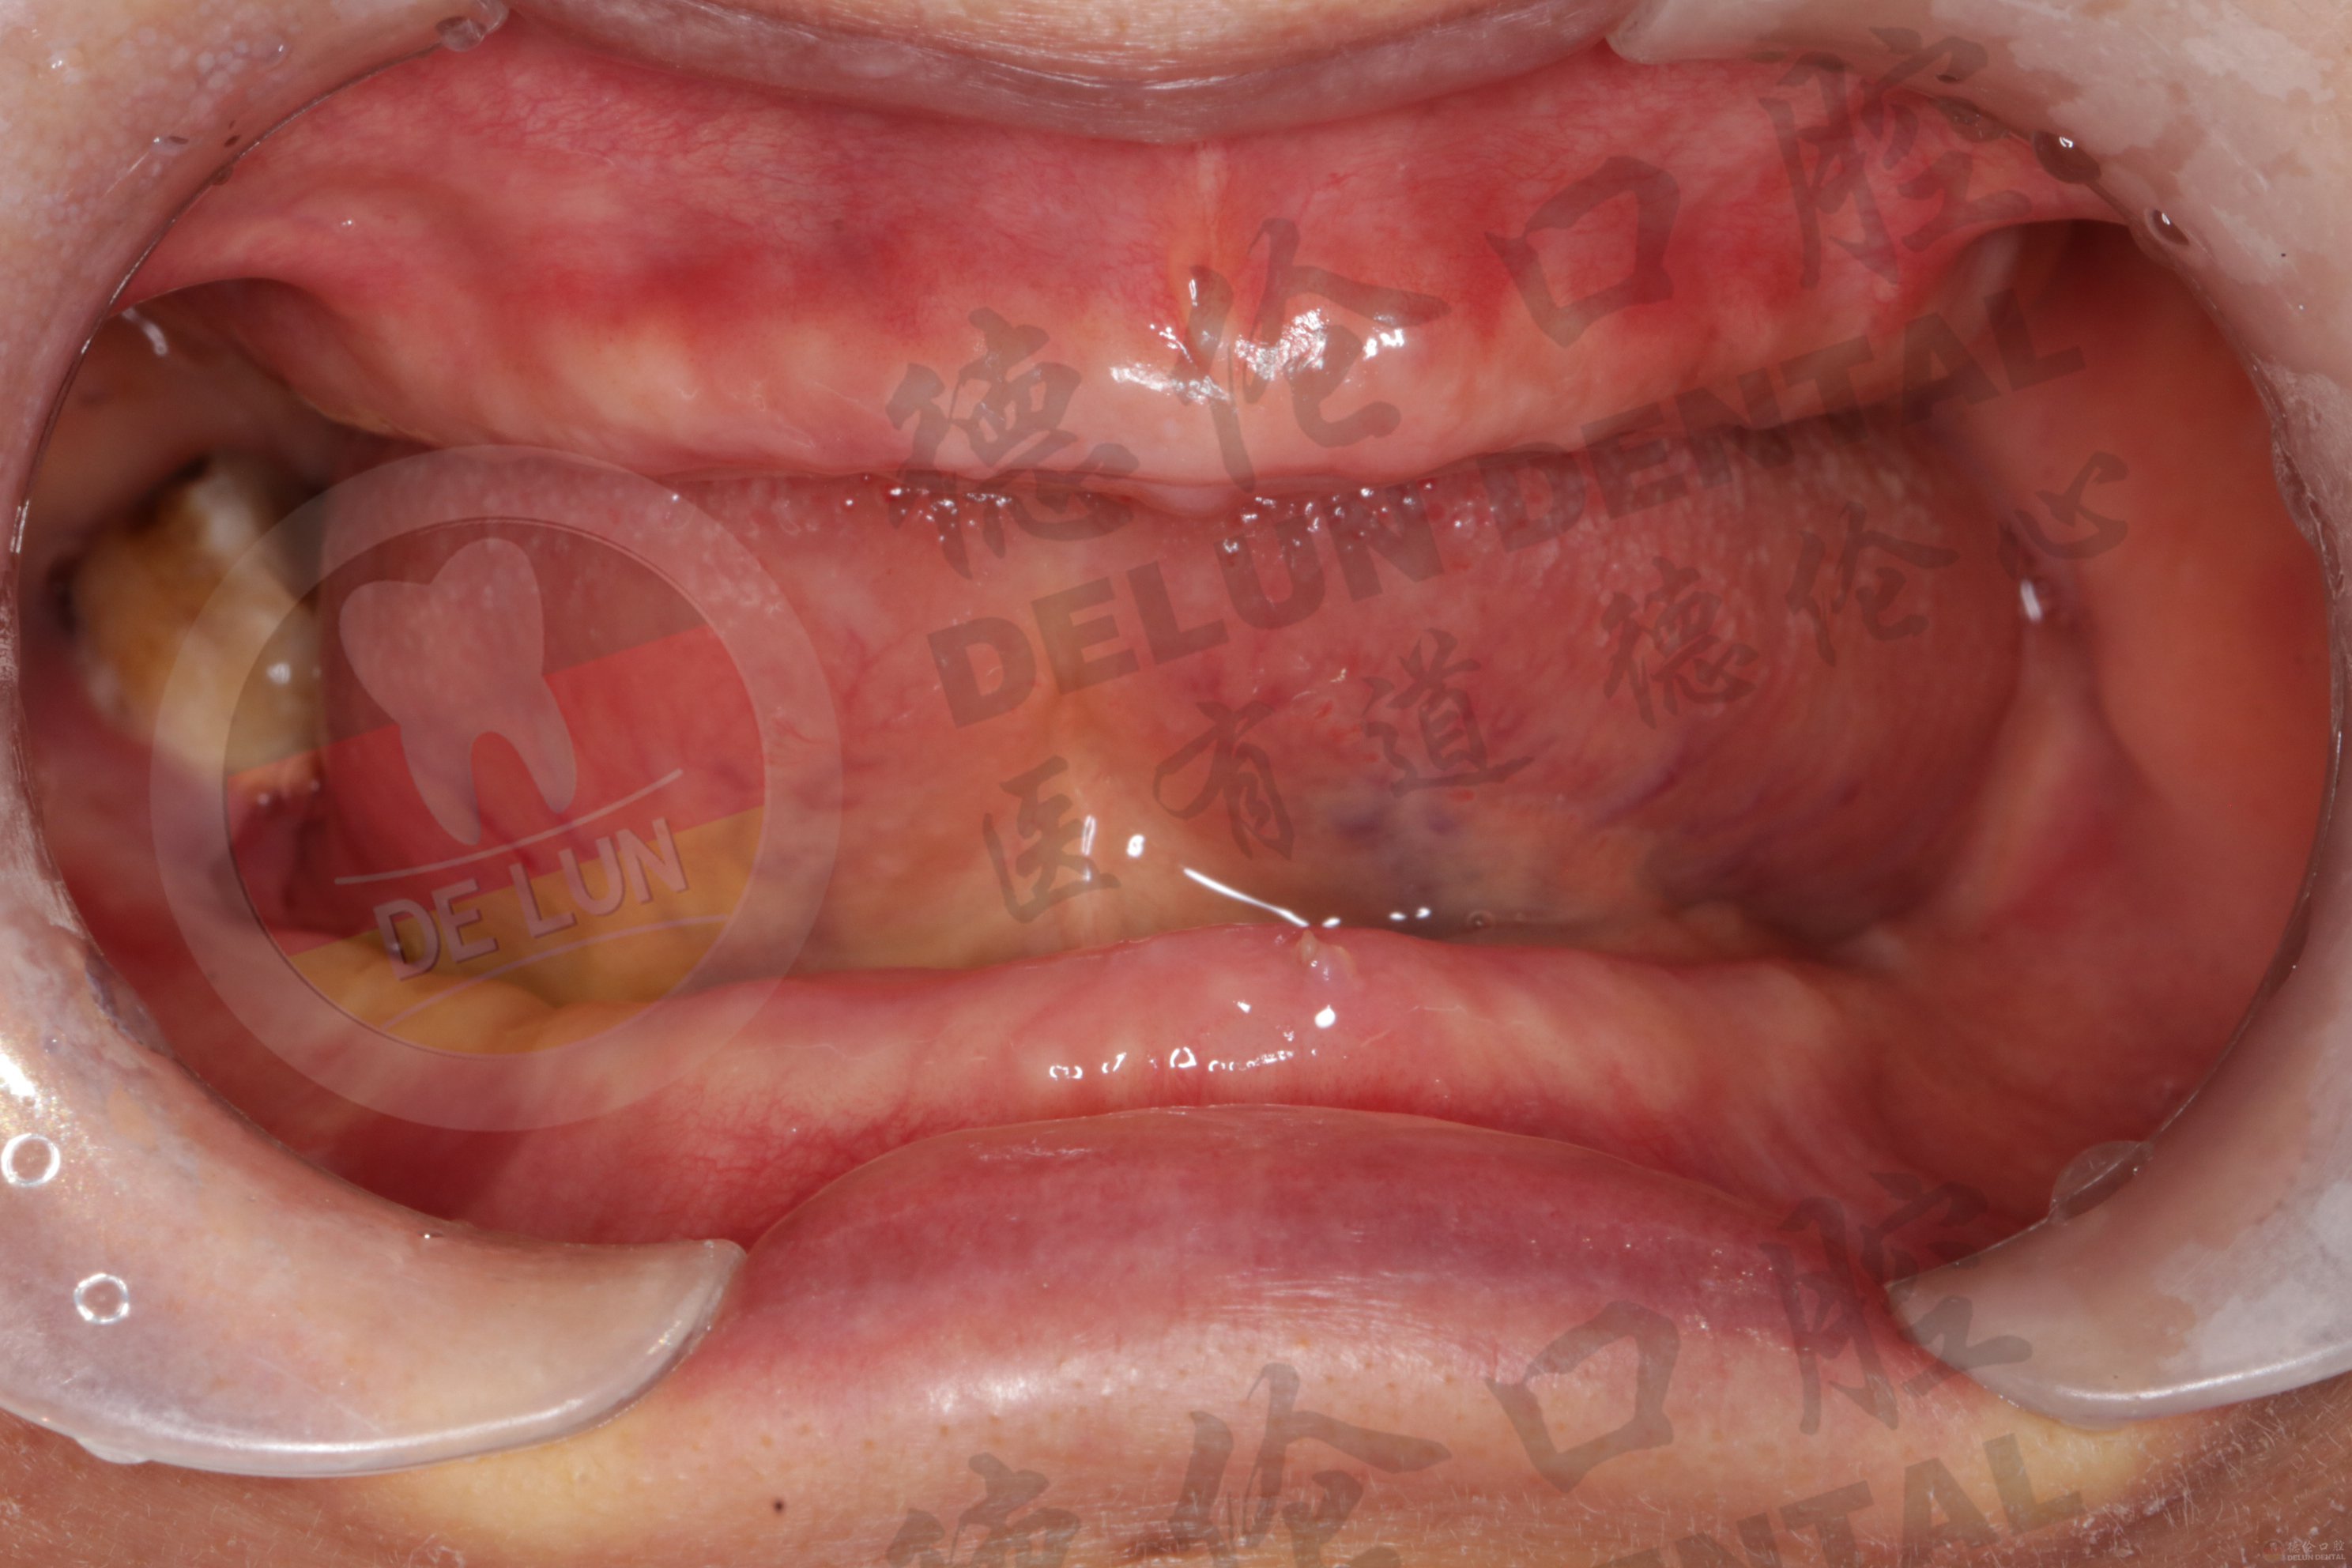

相信大部分老年人都备受掉牙问题困扰,随着年龄渐增原本坚固的牙齿逐渐脱落,甚至出现半口、全口牙缺失,不仅影响美观,日常进食也变得困难。那么,全口牙缺失该怎么办呢?

全口牙缺失患者一般可以采取戴“假牙”或种植牙的方法,解决牙齿缺失问题。如何选择缺牙修复方式?点击咨询>>